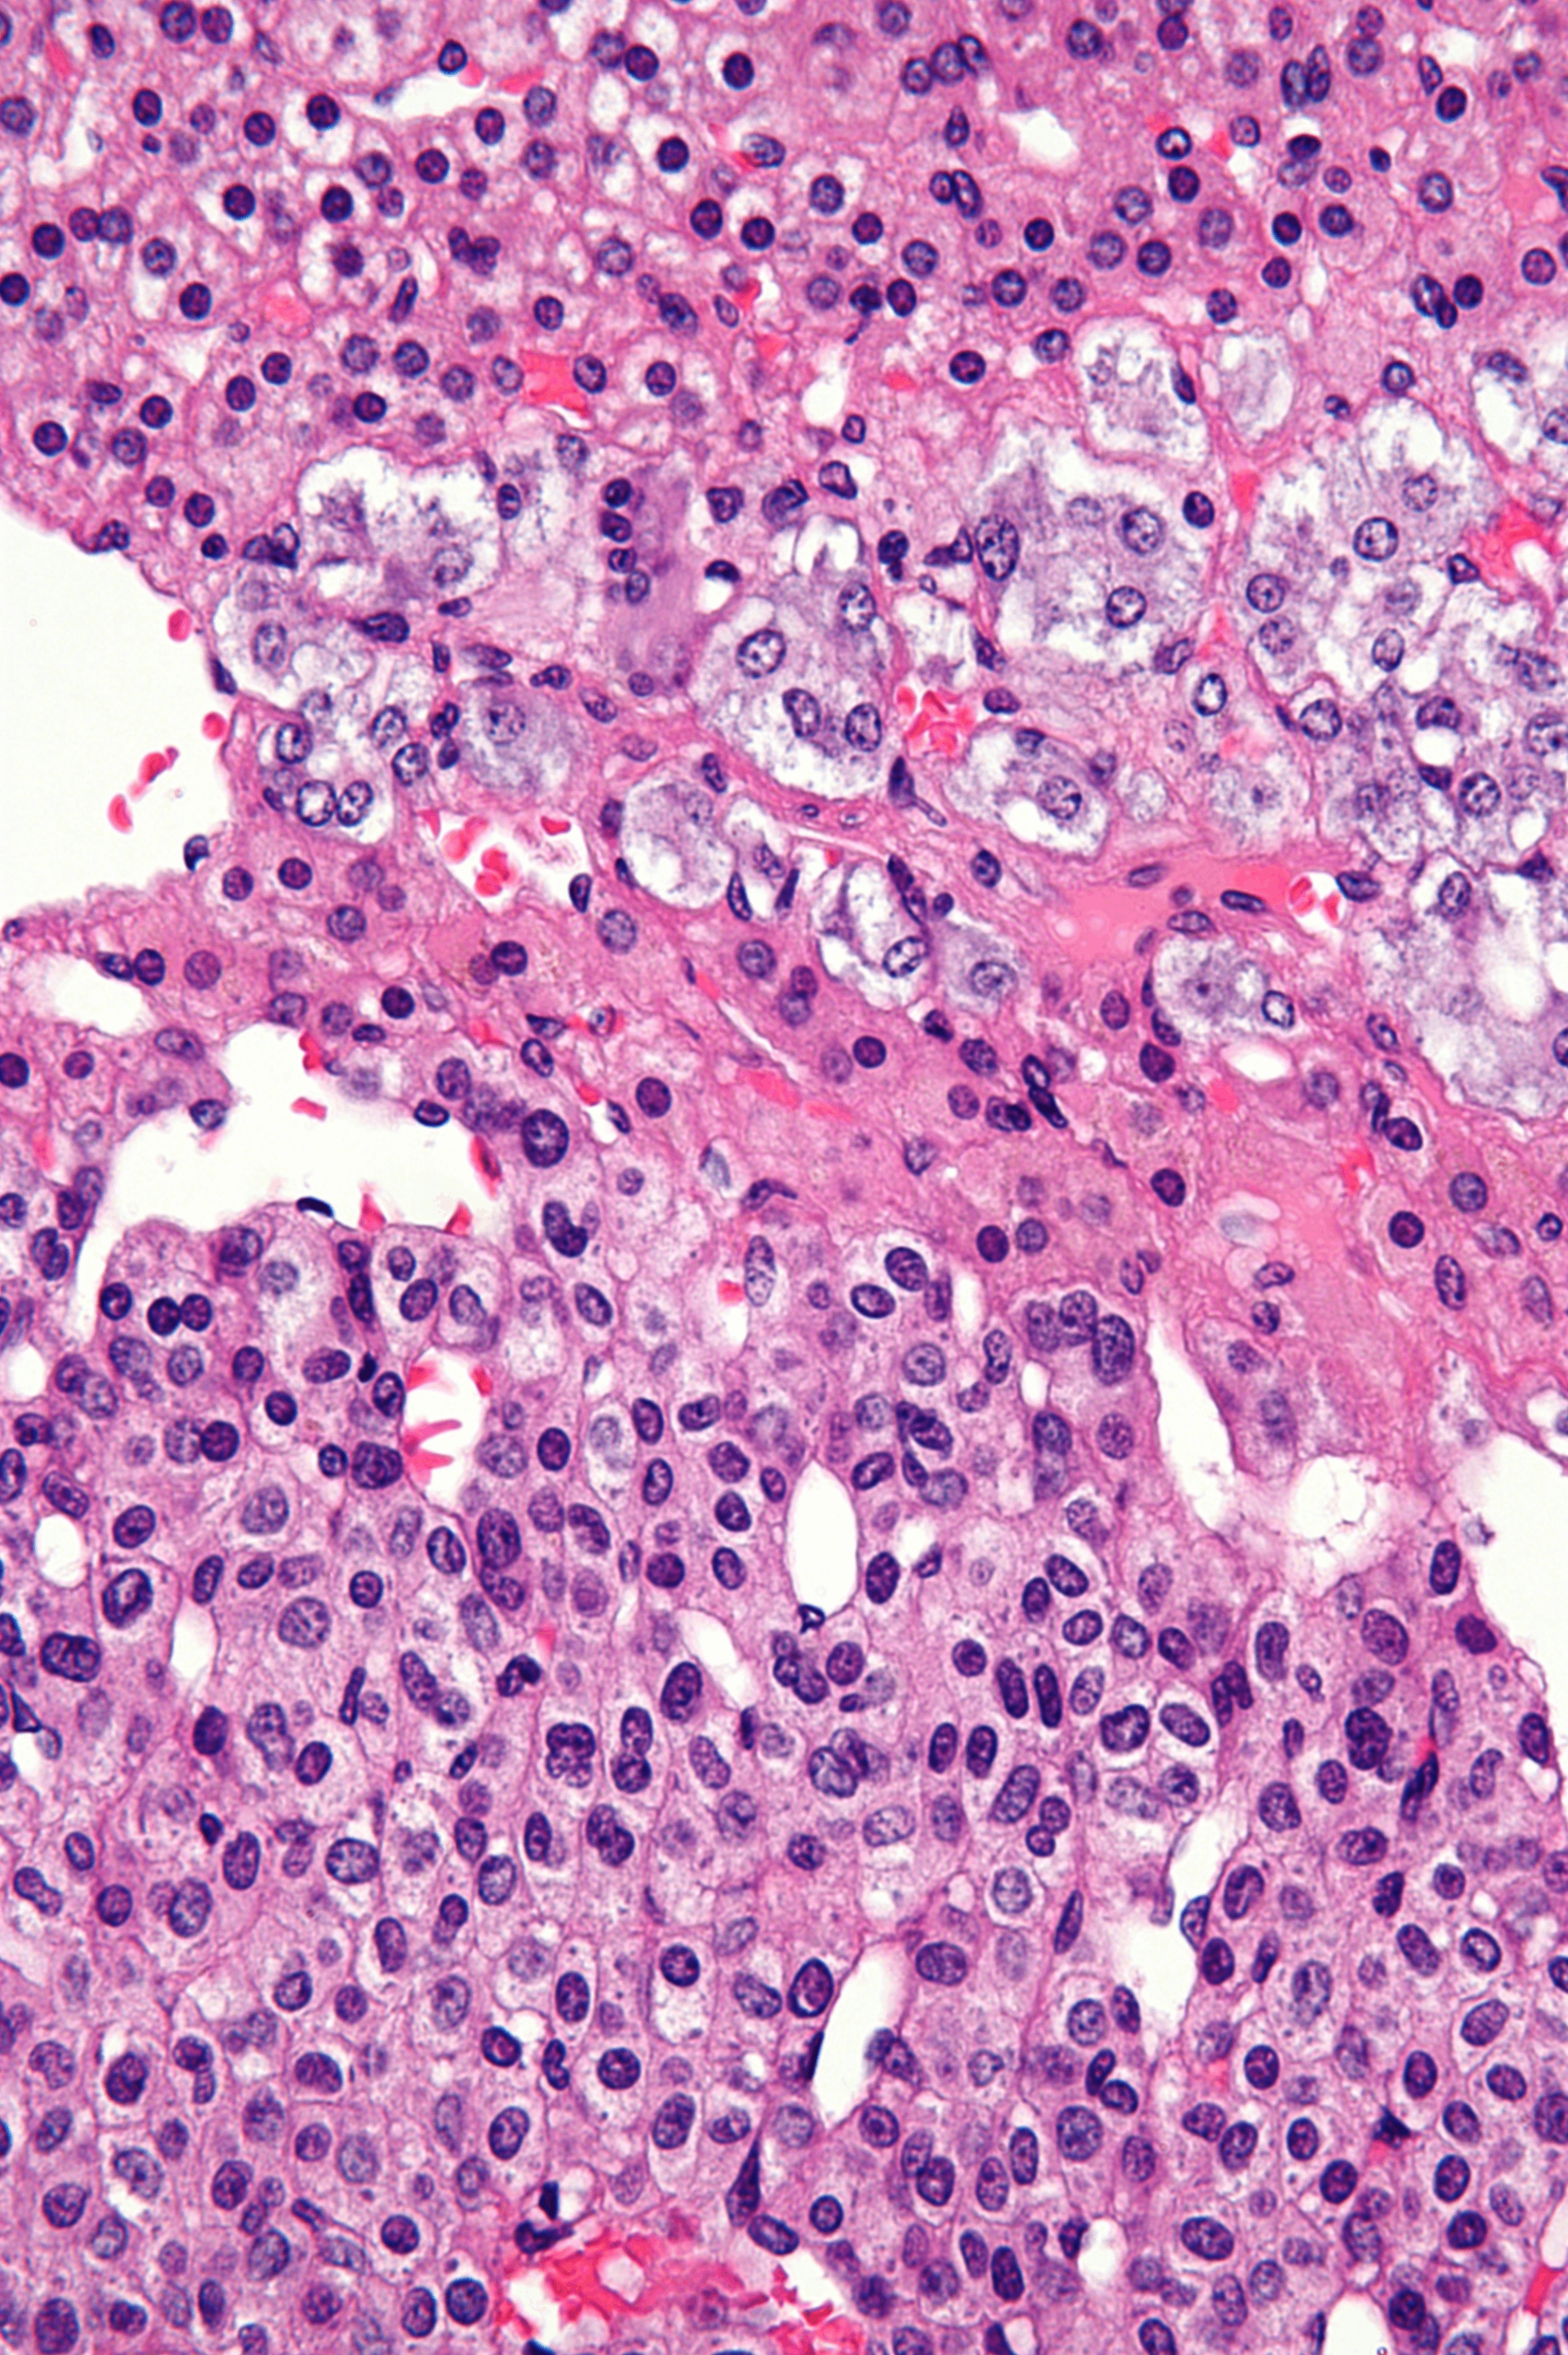

(2) 조직학적 소견

작고 미분화된 원시세포가 sheet 형태로 배열됨; 구성 세포들은 짙은 핵과 적은 세포질(scant cytoplasm)을 보유함

유사분열이 활발하며 핵붕괴(karyorrhexis) 및 다형성(pleomorphism)이 관찰됨

배경에서 신경섬유성 기질(neuropil)이 관찰됨. 이는 신경돌기의 섬유성 성분으로 연한 호산성 섬유질로 나타남

특징적인 구조인 Homer-Wright pseudorosette이 관찰됨; 중심부의 neuropil을 중심으로 종양세포가 동심원 형태로 배열

• Neuro-specific enolase, 전산인자 PHOX2B 양성

Robbins and Cotran Pathologic Basis of Disease, 10e, pg 478